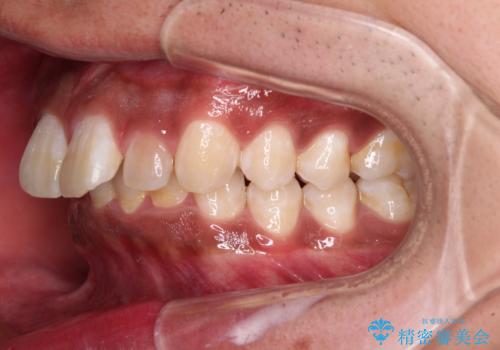

- 深く咬みこみ、前に飛び出した上顎前歯を気にして来院された患者様です。

口元の突出感はあまりありませんでしたが、上顎歯列が全体的に前方にあり、更には下顎歯列が深く咬みこんでいるために、上顎前歯が前方に突出している状態でした。

抜歯は行わず、補助装置を用いて上顎歯列全体を後方移動させ、ワイヤー装置にて奥歯の咬み合わせを改善していくこととしました。